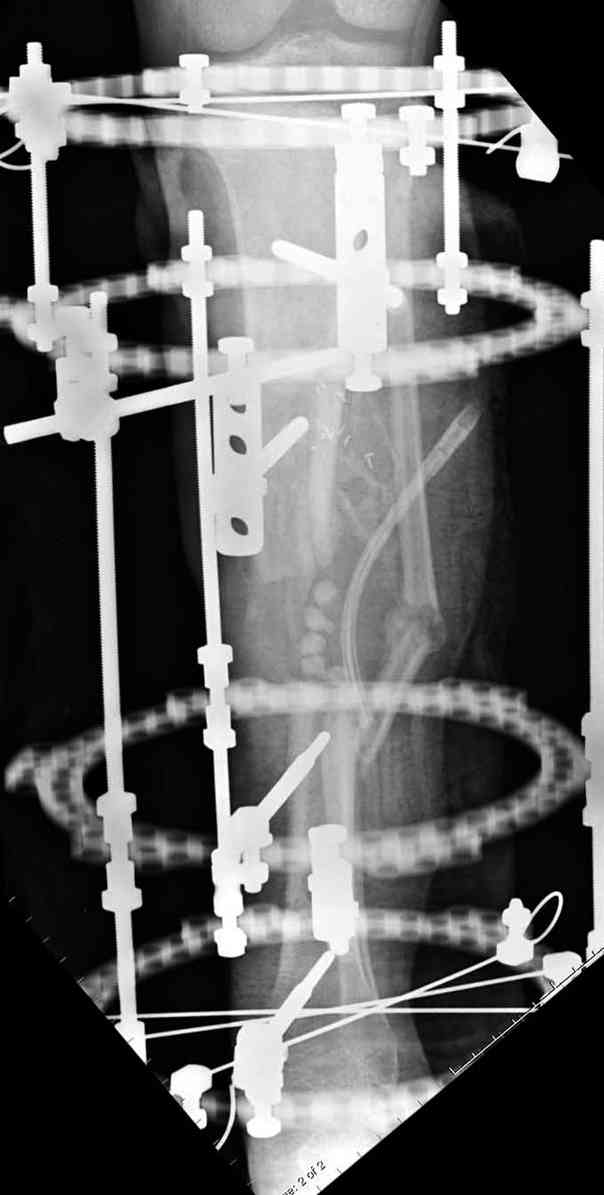

5. Ну и чтобы не быть голословным. Молодой человек подорвался на фугасе (Чечня, 2005 год). Свежие рентгенограммы:

Соответственно ожоги и дефект мягких тканей, переломы костей стопы и пр. Наложили аппарат

Илизарова (как придется), хирургически обработали и героически заживляли мягкие ткани с многочисленными кожными пластиками. В итоге через полгода я принял его вот таким:

Реализовал описанную выше методику, и в итоге вот что получилось. Высылаю лишь прямые проекции,

в боковых тоже всё в тему.

Очень пригодились карбоновые кольца (Джолдас -огромное спасибо, я твой должник!!!), поскольку остеопороз дистального отломка был просто невероятный. На цифровом рентгене с трудом угадывались контуры.

Рентген в процессе перемещения - внизу карбоновые кольца, тракция фрагмента спицами с упором.

внешний вид в аппарате - не завершающем этапе, сначала стопа тоже была фиксирована в аппарате.

Сейчас аппарат сняли, но случай ещё не завершенный.

Признаюсь честно, не совсем уверен в прочности консолидации на стыке косточек. Кроме того, укорочение в районе 6 см. Сейчас реабилитация - ходит опираясь на ногу с одним костылем.

Продолжение, видимо, будет... Возможно, будем удлинять.